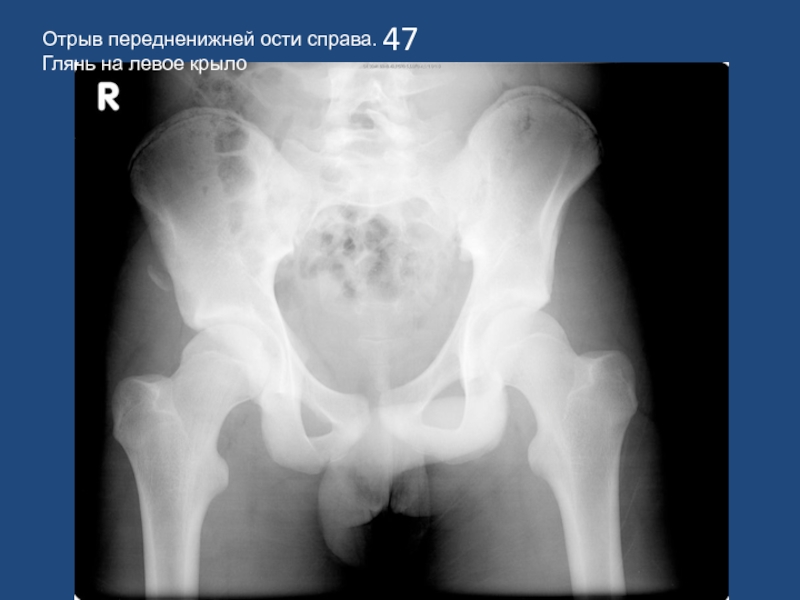

Отрыв передненижней ости справа. Глянь на левое крыло

47Отрыв передненижней ости справа. Глянь на левое крыло